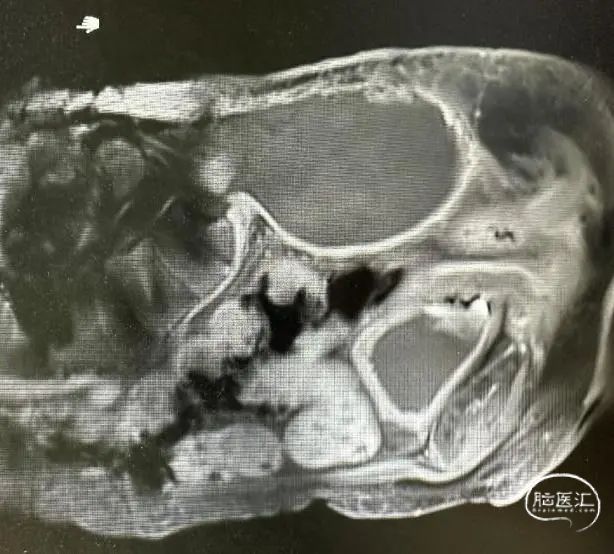

骶尾部巨大占位

骶尾部MRI提示骶尾部巨大占位。